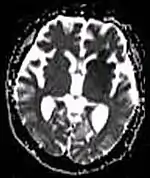

| Fluid-attenuated inversion recovery | FLAIR | Fluid suppression by setting an inversion time that nulls fluids | High signal in lacunar infarction, multiple sclerosis (MS) plaques, subarachnoid haemorrhage and meningitis (pictured).[72] | ![]() | |